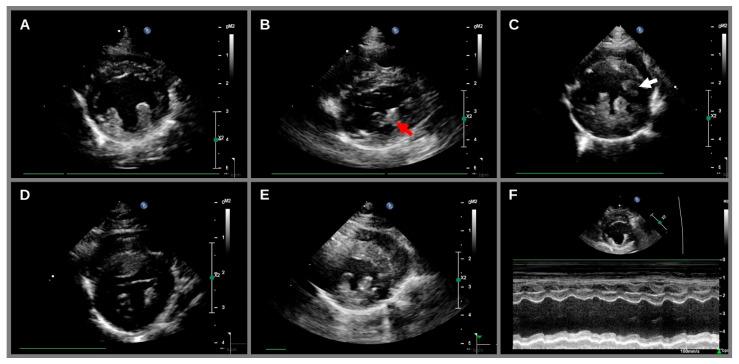

Recently, hypertrophic cardiomyopathy (HCM) in Sphynx cats has been associated with a variant in the gene encoding Alström syndrome protein 1 (ALMS1). The primary aims of this study were to describe the prevalence of HCM in Sphynx cats in New Zealand, and to assess the association between HCM and the ALMS1 variant in this population. In this prospective study, 55 apparently healthy Sphynx cats from registered Sphynx breeders and pet owners in New Zealand were screened by a cardiologist. A total of 42 of these cats had a repeat cardiac examination after median 1.8 years (range: 1.6-2.2). The frequency of the ALMS1 variant was 70.9% (11 homozygous and 28 heterozygous). At the median age of 5.8 years (range: 2.4-13.1), the prevalence of HCM was 40% (20 out of 55 cats). Three cats with HCM died during the study with congestive heart failure. All three cats had focal but extensive myocardial ischemia or infarction at necropsy. The ALMS1 variant was not associated with the HCM diagnosis. In summary, HCM was common in the studied cohort, suggesting Sphynx cats are predisposed to this disease. While the ALMS1 variant was also frequently detected, it was not associated with HCM in this population.

最近,无毛猫的肥厚型心肌病(HCM)与编码阿尔斯特伦综合征蛋白1(ALMS1)的基因变异有关。本研究的主要目的是描述新西兰无毛猫中HCM的患病率,并评估该人群中HCM与ALMS1变异之间的关联。在这项前瞻性研究中,一位心脏病专家对来自新西兰注册无毛猫繁育者和宠物主人的55只看似健康的无毛猫进行了筛查。其中共有42只猫在中位时间1.8年(范围:1.6 - 2.2年)后接受了重复心脏检查。ALMS1变异的频率为70.9%(11只纯合子和28只杂合子)。在中位年龄5.8岁(范围:2.4 - 13.1岁)时,HCM的患病率为40%(55只猫中有20只)。三只患有HCM的猫在研究期间死于充血性心力衰竭。所有三只猫在尸检时均有局灶性但广泛的心肌缺血或梗死。ALMS1变异与HCM诊断无关。总之,HCM在研究队列中很常见,表明无毛猫易患这种疾病。虽然也经常检测到ALMS1变异,但在该人群中它与HCM无关。